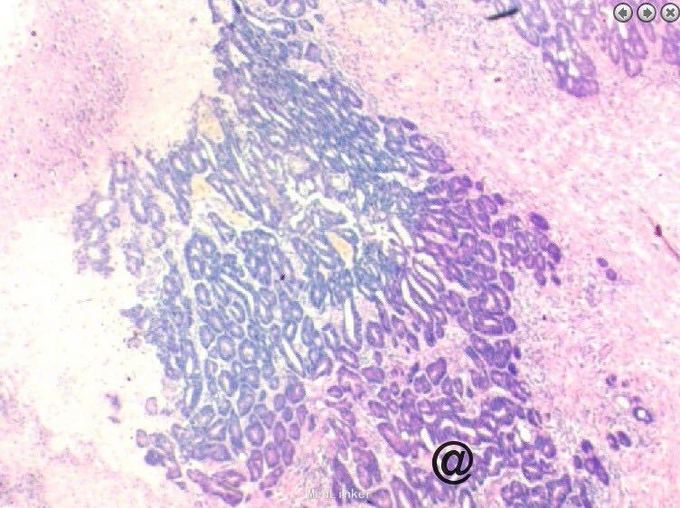

请妇科会诊,该科医师行妇检未见明显包块,且CA125正常,建议行小肠检查,同时行彩超探查了解包块来源,妇科彩超:子宫较小,宫体后壁肌壁间肌瘤(稍凸向宫腔),右侧附件区实质性包块,考虑为右侧卵巢肿瘤,左侧附件区未见明显异常显示,盆腔未见明显积液。 请妇科商议并于患者沟通后于2015.10.08转入妇科,转科行积极完善术前准备,于10.16行剖腹探查术。术中见:子宫稍大,质硬,后壁与直肠致密粘连,左侧卵巢大小正常,右侧卵巢增大直径约4cm,双侧附件与子宫后壁及盆壁致密粘连,分离盆腔粘连后可见巧克力样液体,阑尾可见约9*5*4cm肿瘤,包膜完整,与周围组织无粘连。请胃肠外科主任上台会诊,行阑尾切除术,术中快速病理切片检查示:(阑尾)腺上皮高级别上皮内瘤变(腺上皮中-重度异型增生),确诊待常规。再次向家属交代病情,将快切结果告知患者家属,患者家属了解病情,要求切除右半结肠,切除全子宫及双侧附件,最终行:全麻插管下行右半结肠根治性切除+肠粘连松解+腹式全子宫切除+双侧卵巢输卵管切除术。术后病检提示:(阑尾)中分化腺癌,癌浸润达肌层。阑尾手术切缘未见癌组织。免疫组化:CK19(+),Ki-67 LI约60%。子宫附件及右半结肠:1.送检肠管粘膜组织呈慢性炎,粘膜下水肿,纤维脂肪组织增生,血管扩张、充血。肠周触及淋巴结13枚呈反应性增生。 2.子宫腺肌症,囊性萎缩性子宫内膜组织,慢性子宫颈炎伴鳞状上皮化生。 3.(双侧)卵巢白体形成,(右侧)符合子宫内膜异位囊肿;(双侧)输卵管组织呈慢性炎,(右侧)伴系膜囊肿。